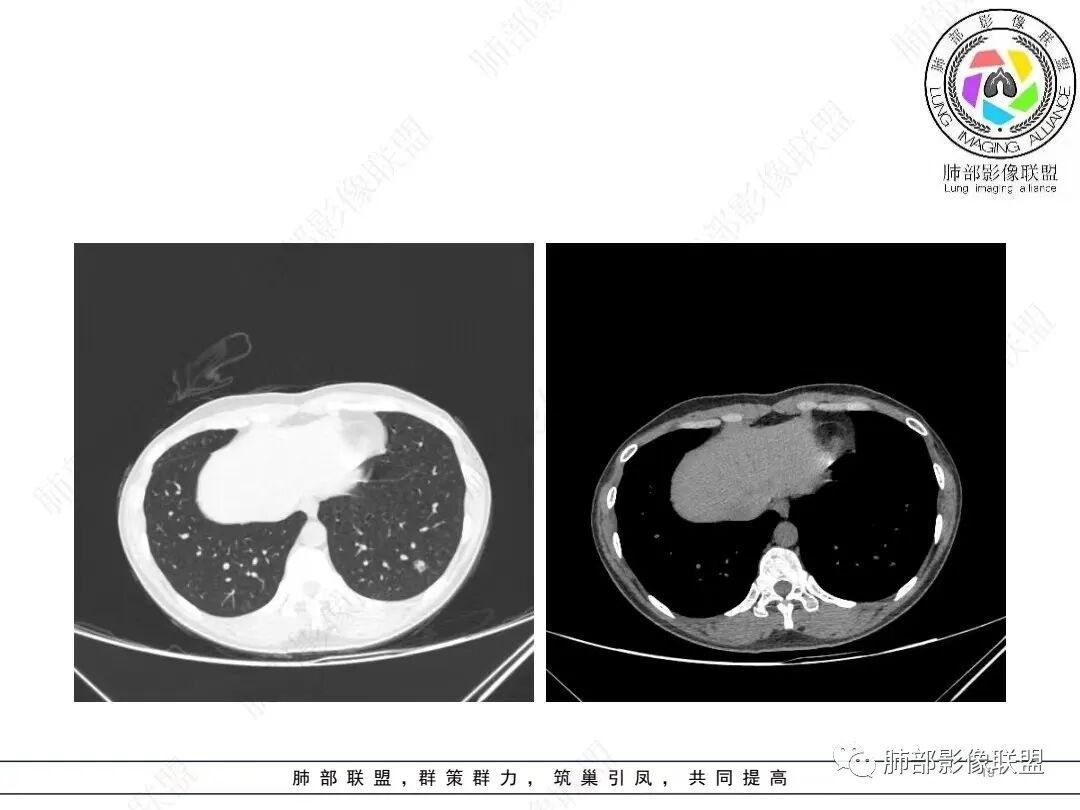

1、临床特点: 37岁女性,体检发现肺结节,2年前有甲状腺腺瘤手术史。实验室无阳性发现。

2、影像特点:左肺下叶类圆形结节影,周围可见多发细小毛刺,浅分叶,张力不高,未见胸膜牵拉。病灶内隐约见空泡影(未提供CT值),近端部分血管呈杵状增粗,可疑脐凹征。增强后实性部分有轻度强化。外围病灶,与支气管关系不明确。

4、病例小结:中青年女性偶然发现结节,表面欠光整,内部空泡,不均匀强化,边缘分叶毛刺等都具有影像学上的恶性征象,正如大多数老师所分析与肺腺癌较为符合。部分肺部肿瘤年轻化,尤其是肺腺癌等应当引发我们高度关注。